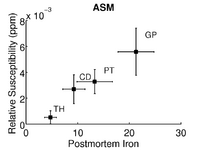

Quantifying magnetic susceptibility in the brain from the phase of the MR signal provides a non-invasive means for measuring the accumulation of iron believed to occur with aging and neurodegenerative disease. Phase observations from local susceptibility distributions, however, are corrupted by external biasfields, which may be identical to the sources of interest. Furthermore, limited observations of the phase makes the inversion ill-posed. We describe a variational approach to susceptibility estimation that incorporates a tissue-air atlas to resolve ambiguity in the forward model, while eliminating additional biasfields through application of the Laplacian. Results show qualitative improvement over two methods commonly used to infer underlying susceptibility values, and quantitative susceptibility estimates show better correlation with postmortem iron concentrations than competing methods.

Results